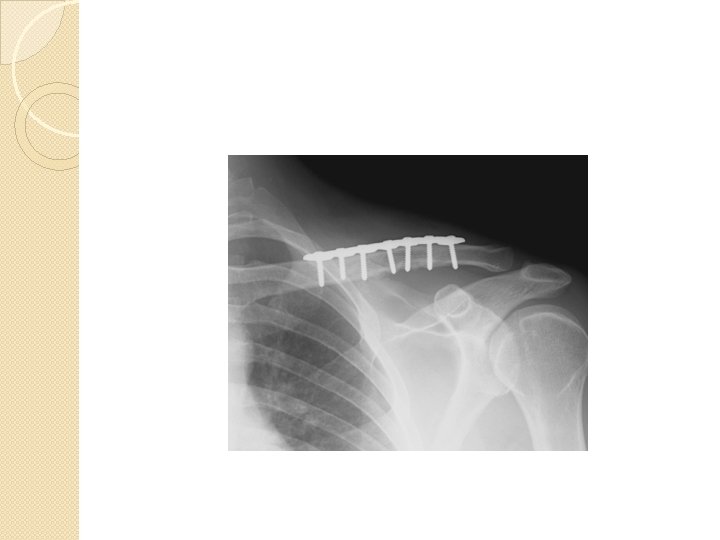

Ligament and Joint Injuries �AC Joint and GH Joint most commonly injured. �Acromioclavicular Joint Sprain ◦ “Separated shoulder” ◦ MOI: impact to top of shoulder; FOOSH; falling on bent elbow shoving head of Humerus up and into AC joint ◦ C/O P w/ ROM, “Step Deformity”

Step Deformity